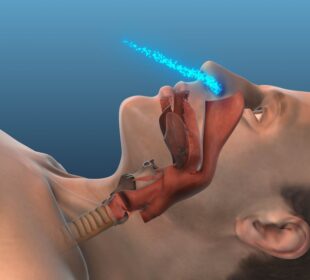

Anglies dioksidas – tai bekvapis ir bespalvis dujų pavidalo junginys, kuris kartais kaupiasi kraujyje esant miego sutrikimams. Ši molekulė sudaryta iš vieno ...Dažniausiai atliekami tyrimai prieš operaciją ir po jos